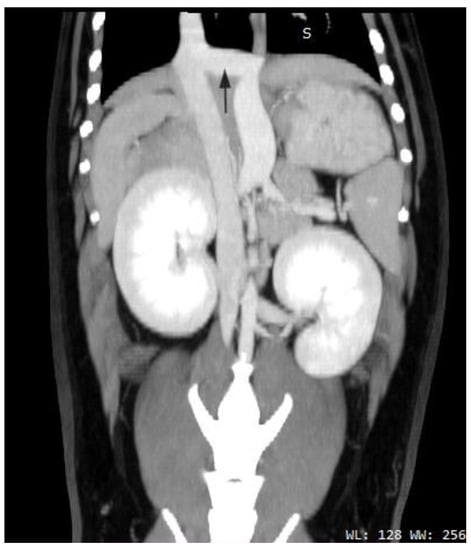

2.1. Case A (Human)

2.2. Case B (Human)